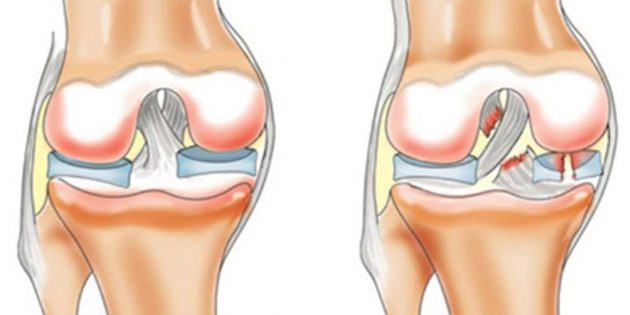

Menisküsün yırtılması

Menisküs, diz ekleminde bir amortisör görevi gören bir kıkırdaktır. Kalınlığı sadece 3-4 mm’dir. Buna rağmen, kıkırdak oldukça dayanıklıdır. Ama yine de savunmasızdır. Örneğin, yüklü bir dizinizi keskin bir şekilde açarsanız, menisküs yırtılabilir. Bunun belirtileri dizde ağrı ve şişliktir. Bununla birlikte, diğer yaralanmaların belirtileri ile de örtüşmektedirler, bu nedenle tanıyı bir uzman koymalıdır.

Ligaman yaralanmaları

ligament (PCL) – diz ekleminde incinme ve uyluk bağlayan dört bağdan biri. Dizin keskin bir dönüşü, mikro çatlaklar veya hatta tam bir yırtılma meydana gelebilir. Bu yaralanma, futbol, basketbol ya da gerektiren diğer sporlarda yer alan kişilerde nadir değildir.